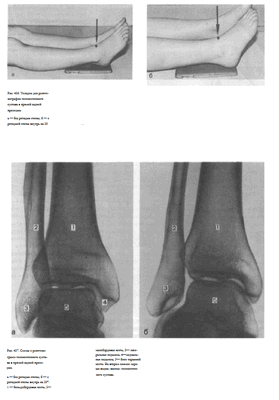

Укладка больного для выполнения снимка. Существуют два варианта укладки для выполнения снимка голеностопного сустава:

1. Снимок голеностопного сустава в прямой задней проекции без ротации стопы. Больной лежит на спине. Ноги вытянуты.

Сагиттальная плоскость стопы исследуемой конечности расположена перпендикулярно к плоскости стола, не отклонена ни кнутри, ни кнаружи. Кассету размером 18x24 см помещают под область голеностопного сустава с таким расчетом, чтобы проекция суставной щели, расположенной на 1 — 2 см выше нижнего полюса медиальной лодыжки, соответствовала бы средней линии кассеты. Пучок рентгеновского излучения направляют отвесно на центр проекции суставной щели голеностопного сустава (рис. 436, а).

2. Снимок голеностопного сустава в прямой задней проекции с ротацией стопы. Укладка отличается от предыдущей положением стопы, которую вместе с голенью ротируют на 15 — 20° кнутри. Положение больного, кассеты и центрация пучка рентгеновского излучения такие же, как и при укладке для снимка голеностопного сустава без ротации стопы

Информативность снимков. На снимках голеностопного сустава в прямой задней проекции выявляются дистальные отделы берцовых костей, медиальная и латеральная лодыжки, блок таранной кости и рентгеновская щель голеностопного сустава латерального отдела голеностопного сустава. Рентгеновская суставная щель на снимке голеностопного сустава с ротацией стопы выглядит в виде буквы «П», при этом ширина ее на всем протяжении одинаковая. Расширение латерального или медиального отдела суставной щели при наличии перелома лодыжек свидетельствует о подвывихе в суставе (рис. 438).

Укладке больного для выполнения снимка. Больной лежит на боку.

Область голеностопного сустава латеральной поверхностью расположена на кассете. Стопу укладывают так, чтобы пятка плотно прилегала к кассете, что обеспечивает поворот стопы внутрь на 15 — 20°. Проекция суставной щели голеностопного сустава соответствует средней линии кассеты. Противоположная конечность согнута в коленном и тазобедренном суставах, перекинута вперед; бедро слегка приведено к животу. Пучок рентгеновского излучения направляют отвесно в центр кассеты через внутреннюю лодыжку (рис. 439).

Информативность снимка. На снимке выявляются дметальные отделы берцовых костей, проекционно накладывающиеся друг на друга, задний край суставной поверхности большеберцовой кости (так называемая «задняя лодыжка»; отрыв которой нередко имеет место при травмах), а также блок таранной кости, пяточная кость. При плотном прилегании наружной поверхности пятки к кассете сагиттальная плоскость стопы устанавливается под углом 15 — 20° к кассете, и на снимке достигается совпадение блоков таранной кости. В таких случаях рентгеновская суставная щель голеностопного сустава имеет форму правильной дуги равномерной ширины на всем протяжении (рис. 440).